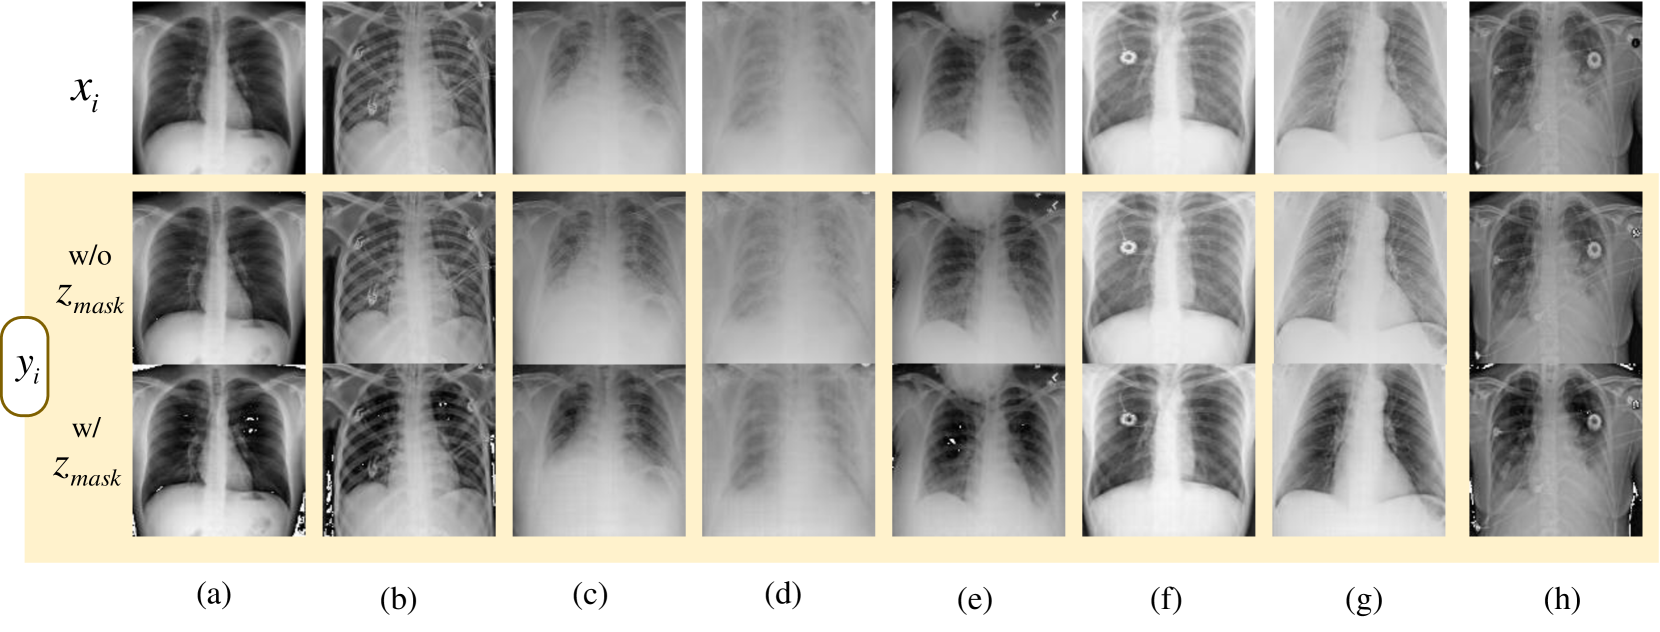

To enhance the learned discrimination with detailed geometrical information, we propose the pixel-level anomaly-removal restoration, as illustrated in the Task II of Fig. 2. Unlike conventional methods that apply image restoration across the entire latent feature space, this task concentrates on localized anomalies by restoring image features that exclude abnormal tokens. Specifically, {Mi,j}j=1Lsuperscriptsubscriptsubscript𝑀𝑖𝑗𝑗1𝐿\{M_{i,j}\}_{j=1}^{L}{ italic_M start_POSTSUBSCRIPT italic_i , italic_j end_POSTSUBSCRIPT } start_POSTSUBSCRIPT italic_j = 1 end_POSTSUBSCRIPT start_POSTSUPERSCRIPT italic_L end_POSTSUPERSCRIPT is utilized to identify anomalies within the latent token features zi,jSsuperscriptsubscript𝑧𝑖𝑗Sz_{i,j}^{\text{S}}italic_z start_POSTSUBSCRIPT italic_i , italic_j end_POSTSUBSCRIPT start_POSTSUPERSCRIPT S end_POSTSUPERSCRIPT (i.e., ‘M’ operation in the Fig 2). We introduce trainable mask tokens, zmasksubscript𝑧𝑚𝑎𝑠𝑘z_{mask}italic_z start_POSTSUBSCRIPT italic_m italic_a italic_s italic_k end_POSTSUBSCRIPT, to replace these abnormal tokens in the latent feature space. Consequently, given the decoder 𝐑𝐑\mathbf{R}bold_R, the restored image can be obtained as follows:

{{yi,j}j=1L}i=1B=𝐑({{z~i,jS}j=1L}i=1B),superscriptsubscriptsuperscriptsubscriptsubscript𝑦𝑖𝑗𝑗1𝐿𝑖1𝐵𝐑superscriptsubscriptsuperscriptsubscriptsuperscriptsubscript~𝑧𝑖𝑗S𝑗1𝐿𝑖1𝐵\displaystyle\{\{y_{i,j}\}_{j=1}^{L}\}_{i=1}^{B}=\mathbf{R}(\{\{\tilde{z}_{i,j% }^{\text{S}}\}_{j=1}^{L}\}_{i=1}^{B}),{ { italic_y start_POSTSUBSCRIPT italic_i , italic_j end_POSTSUBSCRIPT } start_POSTSUBSCRIPT italic_j = 1 end_POSTSUBSCRIPT start_POSTSUPERSCRIPT italic_L end_POSTSUPERSCRIPT } start_POSTSUBSCRIPT italic_i = 1 end_POSTSUBSCRIPT start_POSTSUPERSCRIPT italic_B end_POSTSUPERSCRIPT = bold_R ( { { over~ start_ARG italic_z end_ARG start_POSTSUBSCRIPT italic_i , italic_j end_POSTSUBSCRIPT start_POSTSUPERSCRIPT S end_POSTSUPERSCRIPT } start_POSTSUBSCRIPT italic_j = 1 end_POSTSUBSCRIPT start_POSTSUPERSCRIPT italic_L end_POSTSUPERSCRIPT } start_POSTSUBSCRIPT italic_i = 1 end_POSTSUBSCRIPT start_POSTSUPERSCRIPT italic_B end_POSTSUPERSCRIPT ) , (18)

z~i,jS={zi,jS,if Mi,j=0zmask,if Mi,j=1.superscriptsubscript~𝑧𝑖𝑗Scasessuperscriptsubscript𝑧𝑖𝑗Sif subscript𝑀𝑖𝑗0subscript𝑧𝑚𝑎𝑠𝑘if subscript𝑀𝑖𝑗1\displaystyle\tilde{z}_{i,j}^{\text{S}}=\begin{cases}z_{i,j}^{\text{S}},&% \textit{if }M_{i,j}=0\\ z_{mask},&\textit{if }M_{i,j}=1.\end{cases}over~ start_ARG italic_z end_ARG start_POSTSUBSCRIPT italic_i , italic_j end_POSTSUBSCRIPT start_POSTSUPERSCRIPT S end_POSTSUPERSCRIPT = { start_ROW start_CELL italic_z start_POSTSUBSCRIPT italic_i , italic_j end_POSTSUBSCRIPT start_POSTSUPERSCRIPT S end_POSTSUPERSCRIPT , end_CELL start_CELL if italic_M start_POSTSUBSCRIPT italic_i , italic_j end_POSTSUBSCRIPT = 0 end_CELL end_ROW start_ROW start_CELL italic_z start_POSTSUBSCRIPT italic_m italic_a italic_s italic_k end_POSTSUBSCRIPT , end_CELL start_CELL if italic_M start_POSTSUBSCRIPT italic_i , italic_j end_POSTSUBSCRIPT = 1 . end_CELL end_ROW (19)

We further analyze the impact of other components in Appendix E, such as the contrastive protocol in Task I, the ablation of zmasksubscript𝑧𝑚𝑎𝑠𝑘z_{mask}italic_z start_POSTSUBSCRIPT italic_m italic_a italic_s italic_k end_POSTSUBSCRIPT, and the integration of I(QjbS,,QjiS,)𝐼superscriptsubscript𝑄𝑗𝑏Ssuperscriptsubscript𝑄𝑗𝑖SI(Q_{jb}^{\text{S},-},Q_{ji}^{\text{S},-})italic_I ( italic_Q start_POSTSUBSCRIPT italic_j italic_b end_POSTSUBSCRIPT start_POSTSUPERSCRIPT S , - end_POSTSUPERSCRIPT , italic_Q start_POSTSUBSCRIPT italic_j italic_i end_POSTSUBSCRIPT start_POSTSUPERSCRIPT S , - end_POSTSUPERSCRIPT ).